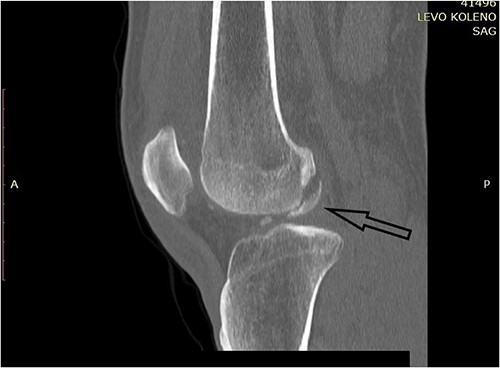

CT scan of the left knee (sagittal) with three fragments (arrows) and patellar fracture (arrowhead).

CT scan of the left knee (sagittal) focusing on the largest posterior fragment (arrow).